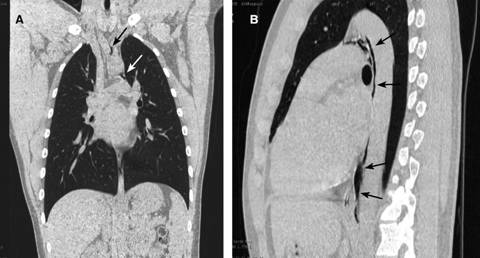

Masculino de 20 años, estudiante, con antecedentes de tabaquismo desde los 16 años (20 cigarrillos/semana), alcoholismo ocasional, deporte tres horas/semana; negó alergias y toxicomanías. Acudió a urgencias manifestando dolor retroesternal moderado, transfictivo, que se irradiaba a la zona interescapular y se incrementaba con la inspiración, de presentación inmediata tras un acceso de tos al momento de levantarse de la cama. Refirió disfagia moderada a la ingestión de líquidos y sólidos. A la exploración: estatura 1.85 m; peso 87 kg; IMC 25.42; FC 85 lat./min; FR 18/min; TA 120/80; Temp. 36.6 oC; cráneo: cara normal; cuello normal sin ingurgitación yugular; tórax con ampliación y amplexación normales; ruidos cardiacos rítmicos acompañados de un crujido áspero sincrónico con el ritmo cardiaco, localizado en todos los focos cardiacos, siendo de mayor intensidad en decúbito lateral derecho (signo de Hamman); los campos pulmonares, con murmullo vesicular normal; el dolor se exacerbaba a la inspiración profunda; abdomen y extremidades normales. Se efectuó un electrocardiograma (normal) y troponina cardiaca seriada a las cuatro y seis horas (siendo indetectable). La tomografía de tórax (Figuras 1 y 2) mostró presencia de aire entre el tronco braquiocefálico y emergencia de la carótida común izquierda y en la ventana aortopulmonar, se extendía caudalmente en íntimo contacto con la aorta descendente y se proyectaba a los vasos supraaórticos (efecto Macklin). Se practicó tránsito esofágico (normal). Con el diagnóstico de neumomediastino espontáneo, se le manejó con reposo, evitando maniobras de Valsalva; se prescribió paracetamol a dosis de 500 mg/TID y oxígeno, tres litros/min por 72 horas. Fue dado de alta asintomático a los cinco días de hospitalización; el signo de Hamman desapareció.

Figura 2: Imágenes de tomografía computada en plano coronal (A) y sagital (B), con presencia de gas entre el tronco braquiocefálico y emergencia de carótida común izquierda (flechas), así como en la ventana aortopulmonar; se extiende caudalmente en íntimo contacto con la aorta descendente (flechas).